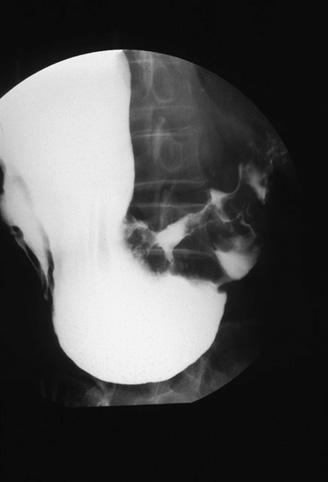

Criteria of Hist.ClassificationMalignant epithelial tumor/Adenocarcinoma

LocationStomach/More than one of above

Technique, MethodX-ray

Macroscopic TypesType 3 Ulcerated type with infiltration/

Size40 -

Depth of Tumor Invasionmuscularis propria